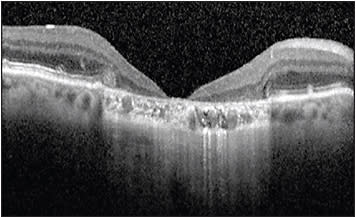

Segmentation algorithms for different commercially available OCT machines vary and are responsible for the variability in automated measurements seen between different OCT machines.3,4 Segmentation algorithms also differ in performance depending on the type of scan and quality of scan performed. In a busy clinical practice, it is not feasible to scroll through entire macular volume scans to identify segmentation errors. Figure 1 shows a case in which manual analysis revealed a substantial increase in maximal macular thickness consistent with a segmentation error. Even if the site identified this segmentation error, manually adjusting segmentation lines could introduce bias to the study. With more detailed analysis including evaluation of segmentation and manual measurement of anatomic features, CRCs have a more comprehensive view not readily available to the clinician.

At times, the site recognizes a segmentation error and requests the CRC to manually correct it. Protocols to handle these errors can vary between different CRCs; however, it is important to limit the bias that could be introduced when manually adjusting segmentation lines and inconsistencies that could occur on future visits if the segmentation line is not placed in the same location.